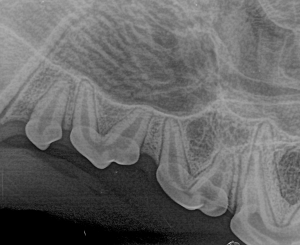

Canine Full Mouth Radiograph Example